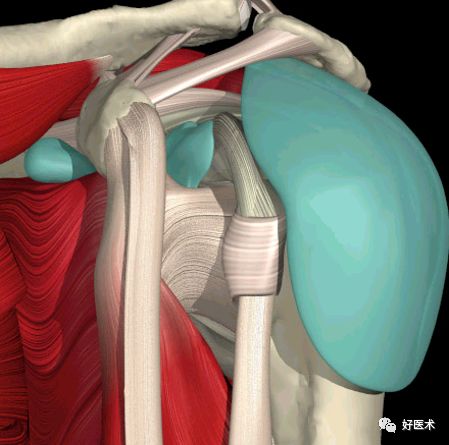

肩 袖:肩袖由四块肌肉和他们的肌腱组成

1. 肩胛下肌

2. 冈上肌

3. 冈下肌

4. 小圆肌